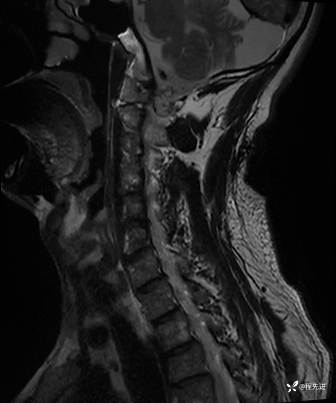

MRI平扫+增强:

T1: